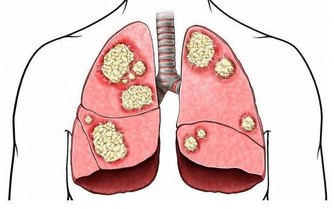

我曾經有位朋友胸口長了一顆痘,痘痘消退後,摸上去裡邊似乎什麼也沒有,也無痛感。

但三四個月過去後,她發現那顆痘印一直未消,保持著原來的顏色。

一日她覺得好奇,便取來粉刺針,稍挑破了點皮按壓痘印處,

結果一條一條細長的白色泥狀物,綿綿不斷地從皮膚裡冒出來,

足足擠了四次才徹底擠乾淨,把她給嚇傻了,也看噁心了。

她沒法想像一顆看似消退的痘痘,

那麼丁點兒大的皮膚之下,竟然隱藏了如此多的髒物。

所以,如果看似消退的痘痘、痘印久不退色,

不妨看看裡面是否藏有污垢,只有徹底清理乾淨痘痘才能真正消退。